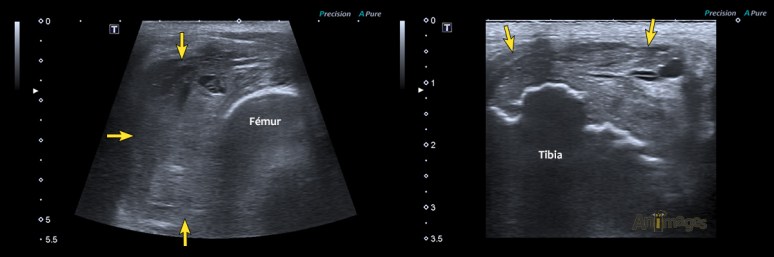

Dans le cas présent, une échographie a démontré que la zone d’enflure au pourtour du grasset correspondait à une masse hypoéchogène au contour irrégulier qui était accolée à toutes les structures osseuses du grasset (flèches jaunes dans la figure ci-bas). Plusieurs foyers de prolifération osseuse étaient notés ainsi que plusieurs foyers de lyse corticale parmi lesquels s’infiltraient la masse. Cet examen a confirmé la suspicion clinique de néoplasme articulaire agressif, compatible avec un sarcome synovial.